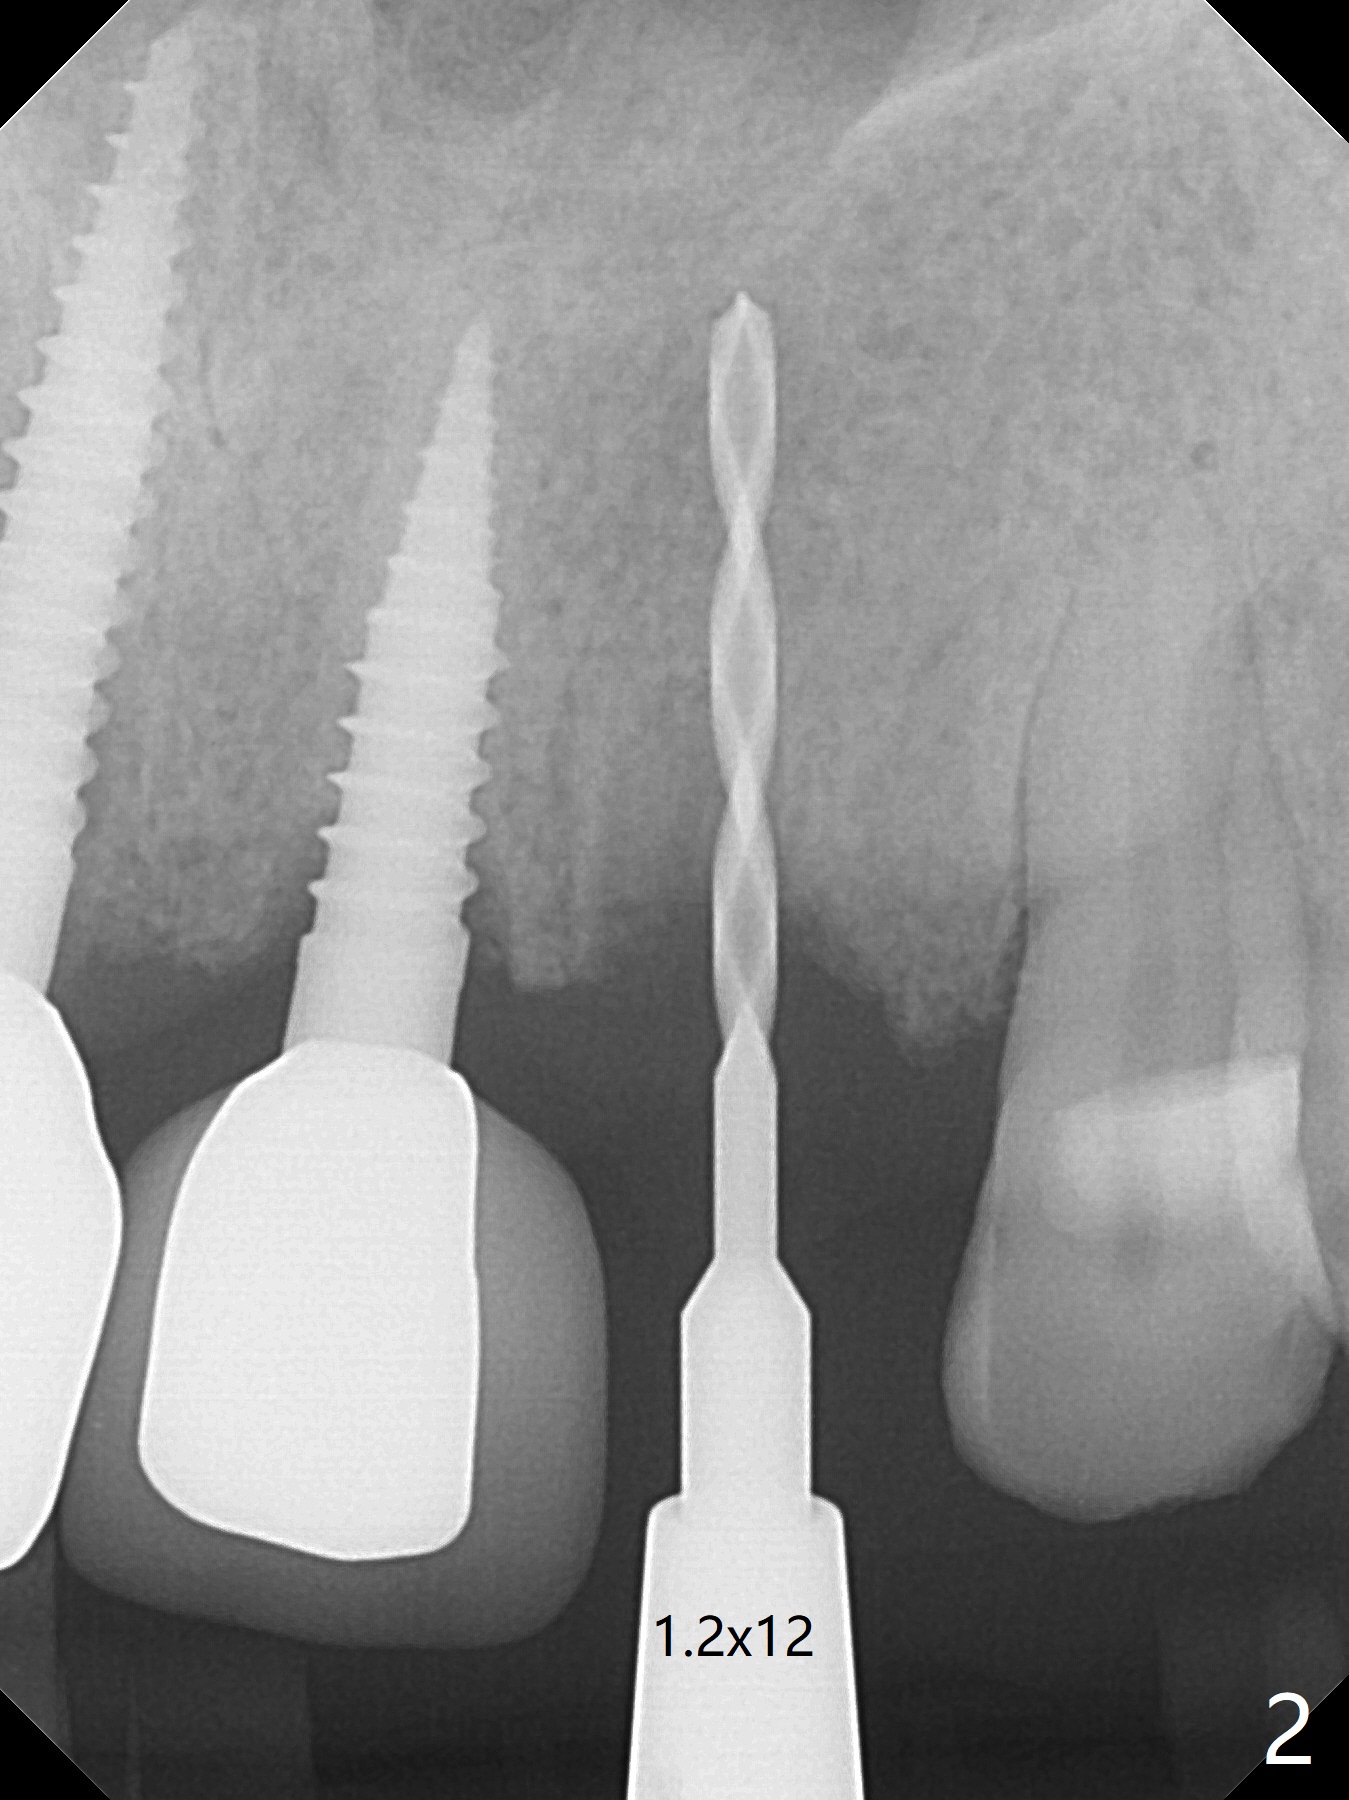

A 64-year-old man requests implant for the loose tooth at #10. The bone width is 5.5 mm (Fig.1); with 2.5 mm implant, there is 1.5 mm of the bone on the either side of the implant. The ideal width is 2 mm, which is safe, preventing buccal or palatal plate perforation. The buccal crest is lower when the tooth is extracted (Fig.4). Following trajectory confirmation (Fig.2), a 2.5x12(2) mm implant is placed a little deeper than expected to ensure no implant thread exposure with bone graft (Fig.3,5). The bone loss at #8 and 9 (Fig.2,3) is associated with the narrow ridge. The surface treatment of 1-piece implants is not as good as that of regular ones. The threads appears to be covered by the bone or bone graft 4 months postop (Fig.6).